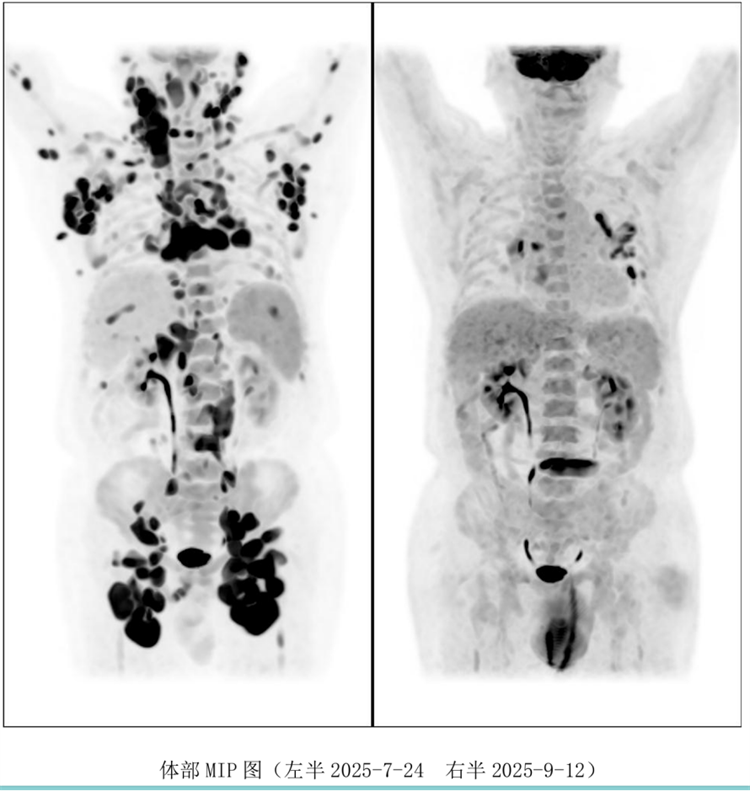

病例汇报环节由我院淋巴瘤科张薇医生带来了三例精彩纷呈的难治复发弥漫大B淋巴瘤CAR-T治疗的病例。

病例过程跌宕起伏,从桥接治疗到靶点的选择,并发症的处理都极具代表性。张医生详尽分享了患者在治疗过程中的挑战、决策依据以及CAR-T细胞治疗后的惊人缓解与转归,充分展示了CAR-T技术为晚期患者带来的突破性生存希望。